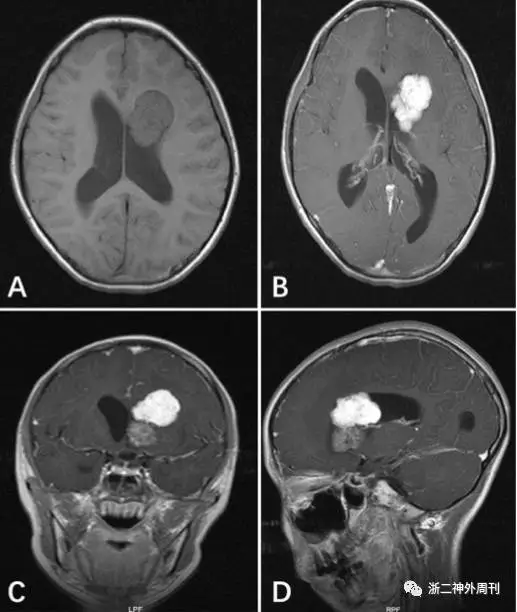

入院后完善头颅增强MRI检查:头颅增强MRI示左侧侧脑室前角占位,考虑脉络丛乳头状瘤。(大体:肿瘤瘤块突入侧脑室,局限性生长,可见钙化)(图1)。

图1. A.增强MRI见左侧侧脑室前角占位,大小30mmX37mmX48mm(左右X前后X上下)B.双侧侧脑室、第三脑室、第四脑室扩张。中线结构居中。C.D.呈多发结节状,边界清晰